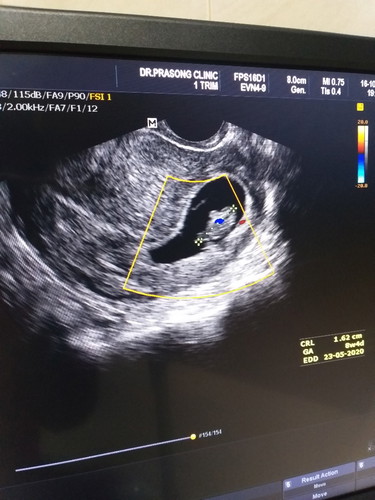

ความสุขของคนเป็นแม่ คือได้เห็น.. "ภาพจากอัลตราซาวนด์"ครั้งแรก 8week4day♡